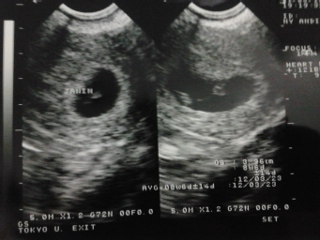

Berikut beberapa foto USG yang menggambarkan pertumbuhan my baby in the womb:

| 7 week |

| 15 week |

| 25 week |